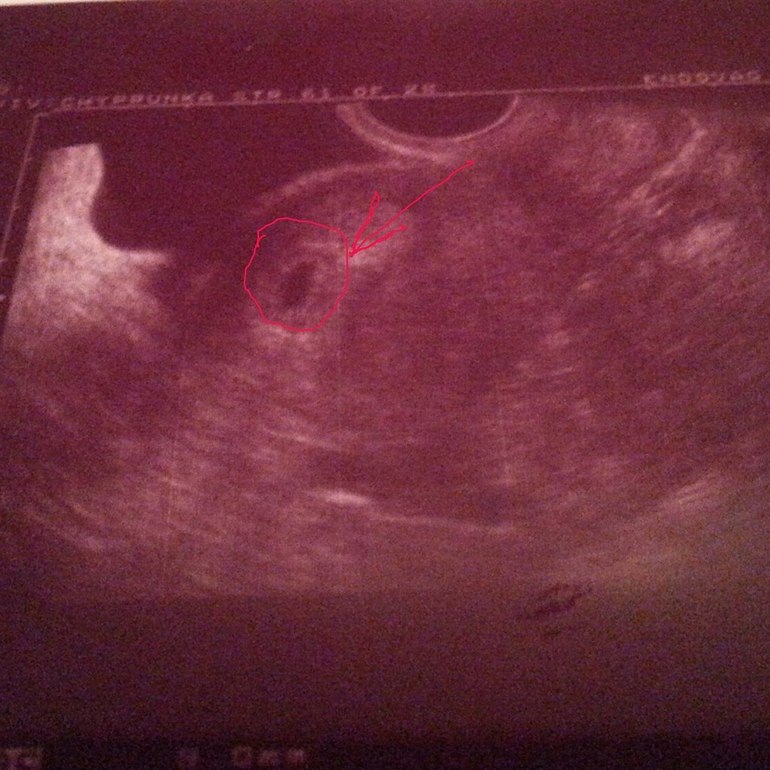

УРА! Официально беременна!

Нашли сегодня мою крошку, там где надо))ПЯ =9,8 мм, желточный мешочек d=4,0 мм, поставили строк 3-4 недели от зачатия)) Эндометрий хороший!)Я очень счастлива, надеюсь и дальше все будет развиваться хорошо))